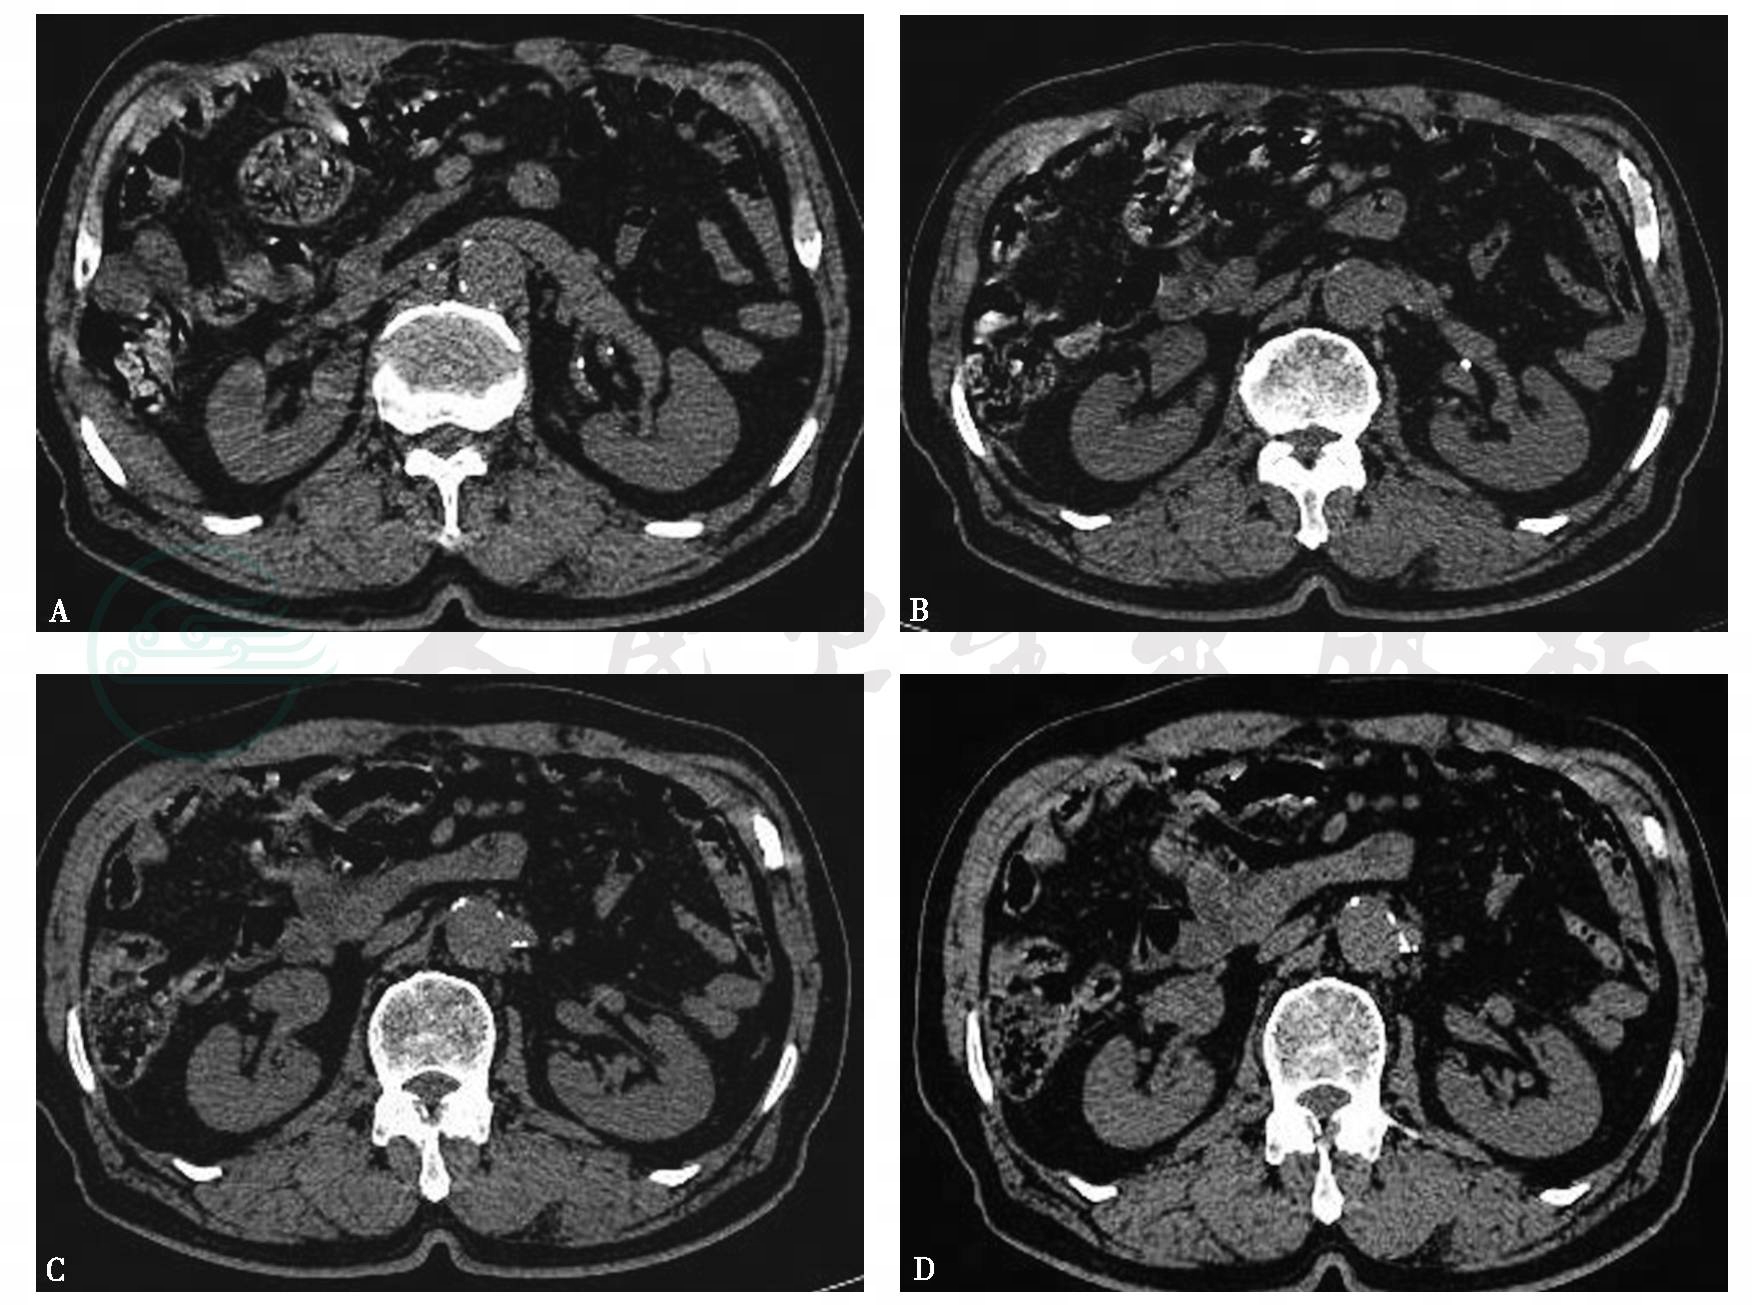

图1肾动脉粥样硬化

A~D.左肾动脉起始处及肾门处血管壁可见多发点状高密度影,边缘清晰